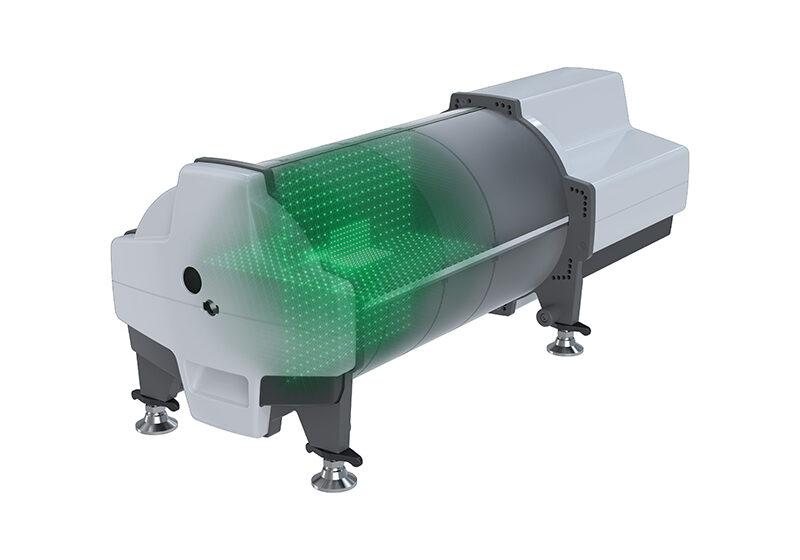

Delta4 Phantom+ MR

The Delta4 Phantom+ for MR-linacs

The Delta4 Phantom+ MR is an innovative device for addressing pre-treatment quality assurance (QA) for highly modulated radiotherapy treatment plans in MR-linacs.

It is the ONLY system that measures the dose distribution in the isocentric region and not simply in one single flat or wrapped plane.

The patented geometric, dual orthogonal detector planes and the nature of the detectors make the Delta4 Phantom+ MR a unique quality assurance system.

MR compatible

- Up to 1.5T MRI

- Compatible with Elekta Unity

- Compatible with Viewray MRIdian

- Isocentric measurements in two orthogonal detector planes

- 1069 p-type silicon diodes

- Resolution 5 mm at isocenter, can be increased to 2.5 mm by merging

Superior detectors